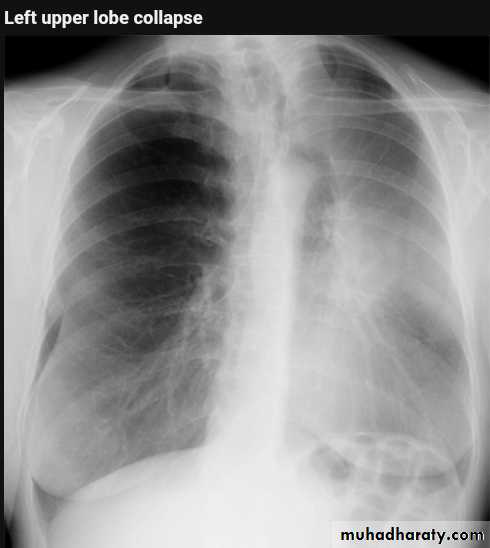

Left upper lobe collapse has distinctive features but can be challenging to identify on chest radiographs by the uninitiated.

Radiographic features

The left upper lobe collapses anteriorly becoming a thin sheet of tissue apposed to the anterior chest wall, and appears as a hazy or veiling opacity extending out from the hilum and fading out inferiorly . It thus reverses the normal slight increase in radiographic density seen as you move down the lung (due to increased thickness of the chest soft tissues).

Parts of the normal cardiomediastinal contour may also be obliterated where the left upper lobe, particularly the lingula abut the left heart border. The anterior parts of the aortic arch are also often obliterated from view.

In some cases the hyperexpanded superior segment of the left lower lobe insinuates itself between the left upper lobe and the superior mediastinum, sharply silhouetting the aortic arch and resulting in a lucency medially. This is known as the HYPERLINK "http://radiopaedia.org/articles/luftsichel-sign" luftsichel sign.

The left hilum is also drawn upwards, resulting in an almost horizontal course of the left main bronchus and vertical course of the left lower lobe bronchus.

Non-specific signs indicating left sided atelectasis will also be present, including:

elevation of the hemidiaphragm

'peaked' or 'tented' hemidiaphragm: HYPERLINK "http://radiopaedia.org/articles/juxtaphrenic-peak-sign" juxtaphrenic peak sign

crowding of the left sided ribs

shift of the mediastinum to the left

On lateral projections the left lower lobe is hyperexpanded and the oblique fissure displaced anteriorly. There is associated increase in the retrosternal opacity.